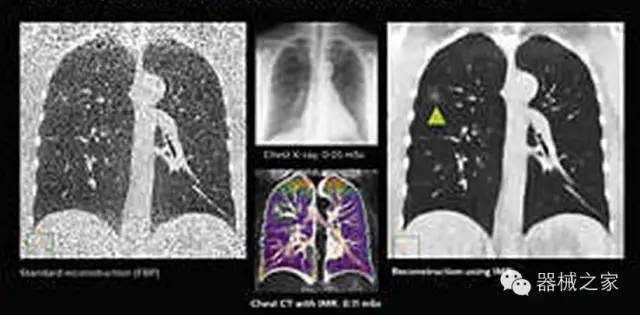

1.低劑量下的胸部顯影

透過數(shù)字化影真芯片DAS系統(tǒng)、球面微平板探測器技術(shù)和濾線柵技術(shù)等硬件技術(shù),整體提高探測器成像的能力,奠定低劑量條件下高清成像的基礎(chǔ);

應(yīng)用目前業(yè)界領(lǐng)先的新一代星光平臺iDose4 Premium及基于迭代基礎(chǔ)的O一MAR去除金屬偽影技術(shù),達(dá)成微量輻射下零偽影的高清晰成像;